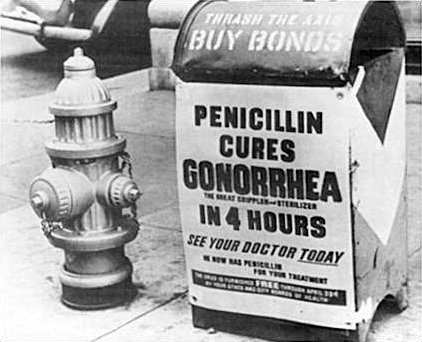

1928年

Alexander Fleming(弗莱明)发现了盘尼西林,就是著名的青霉素。这可能是历史上最偶然的科学发现。在研究各型葡萄球菌时,弗莱明将一些培养皿置于实验台上以用于日后观察。几天后,他发现培养物被霉菌孢子所污染,但惊奇地发现,在霉菌孢子生长的区域,葡萄球菌被击退了。尽管弗拉明已经发现了青霉素,但是正式的临床应用却在十年以后,因为制造青霉素很难,并且青霉素对其它细菌性感染的治疗作用还没有被认可。1940年代,德国开始侵犯欧洲,牛津的一群科学家的工作使大规模生产青霉素称为可能,并且最终认识到了青霉素的强大疗效。